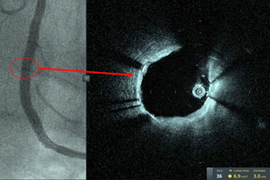

‘World-first’ treatment of patient with high-frequency OCT for cardiology intervention

Technique used at Tampa General Hospital to help place three stents; method enables smaller catheter to be inserted.